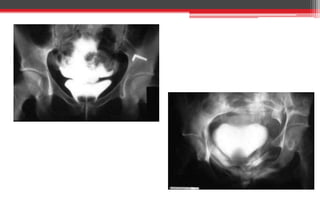

• If there is blood at the external meatus or the urine is blood-

stained, a urethrogram using water-soluble contrast material may

demonstrate the extravasation BUT may worsen the injury.

Investigations

• Ascending and descending urethrogram to

demonstrate the urethral anatomy.